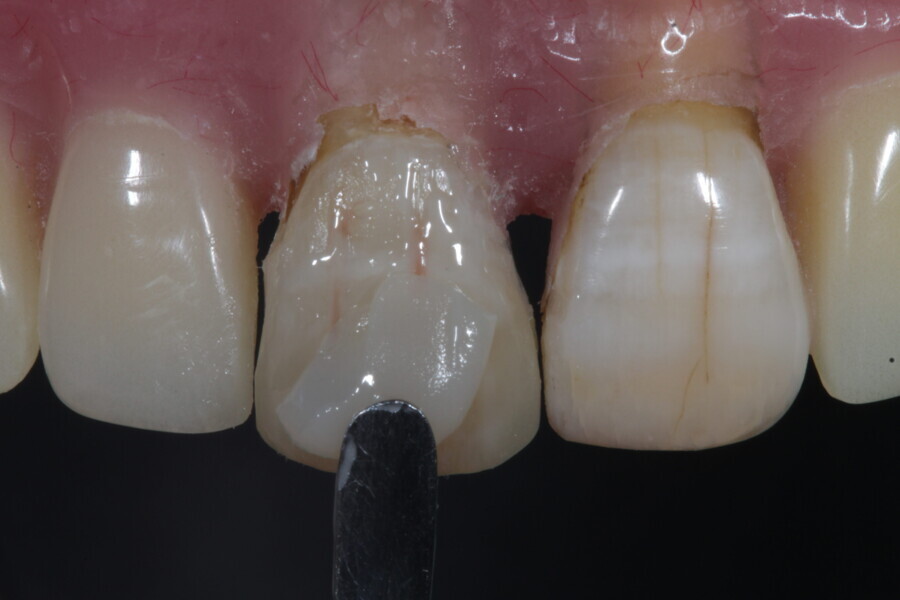

1. functional and aesthetic reconstruction of a maxillary anterior tooth using fibre-reinforced flexible micro-posts after endodontic treatment (Figs. 3–20);

Example 1—showing functional and aesthetic reconstruction of a maxillary anterior tooth using fibre-reinforced flexible micro-posts after endodontic treatment.